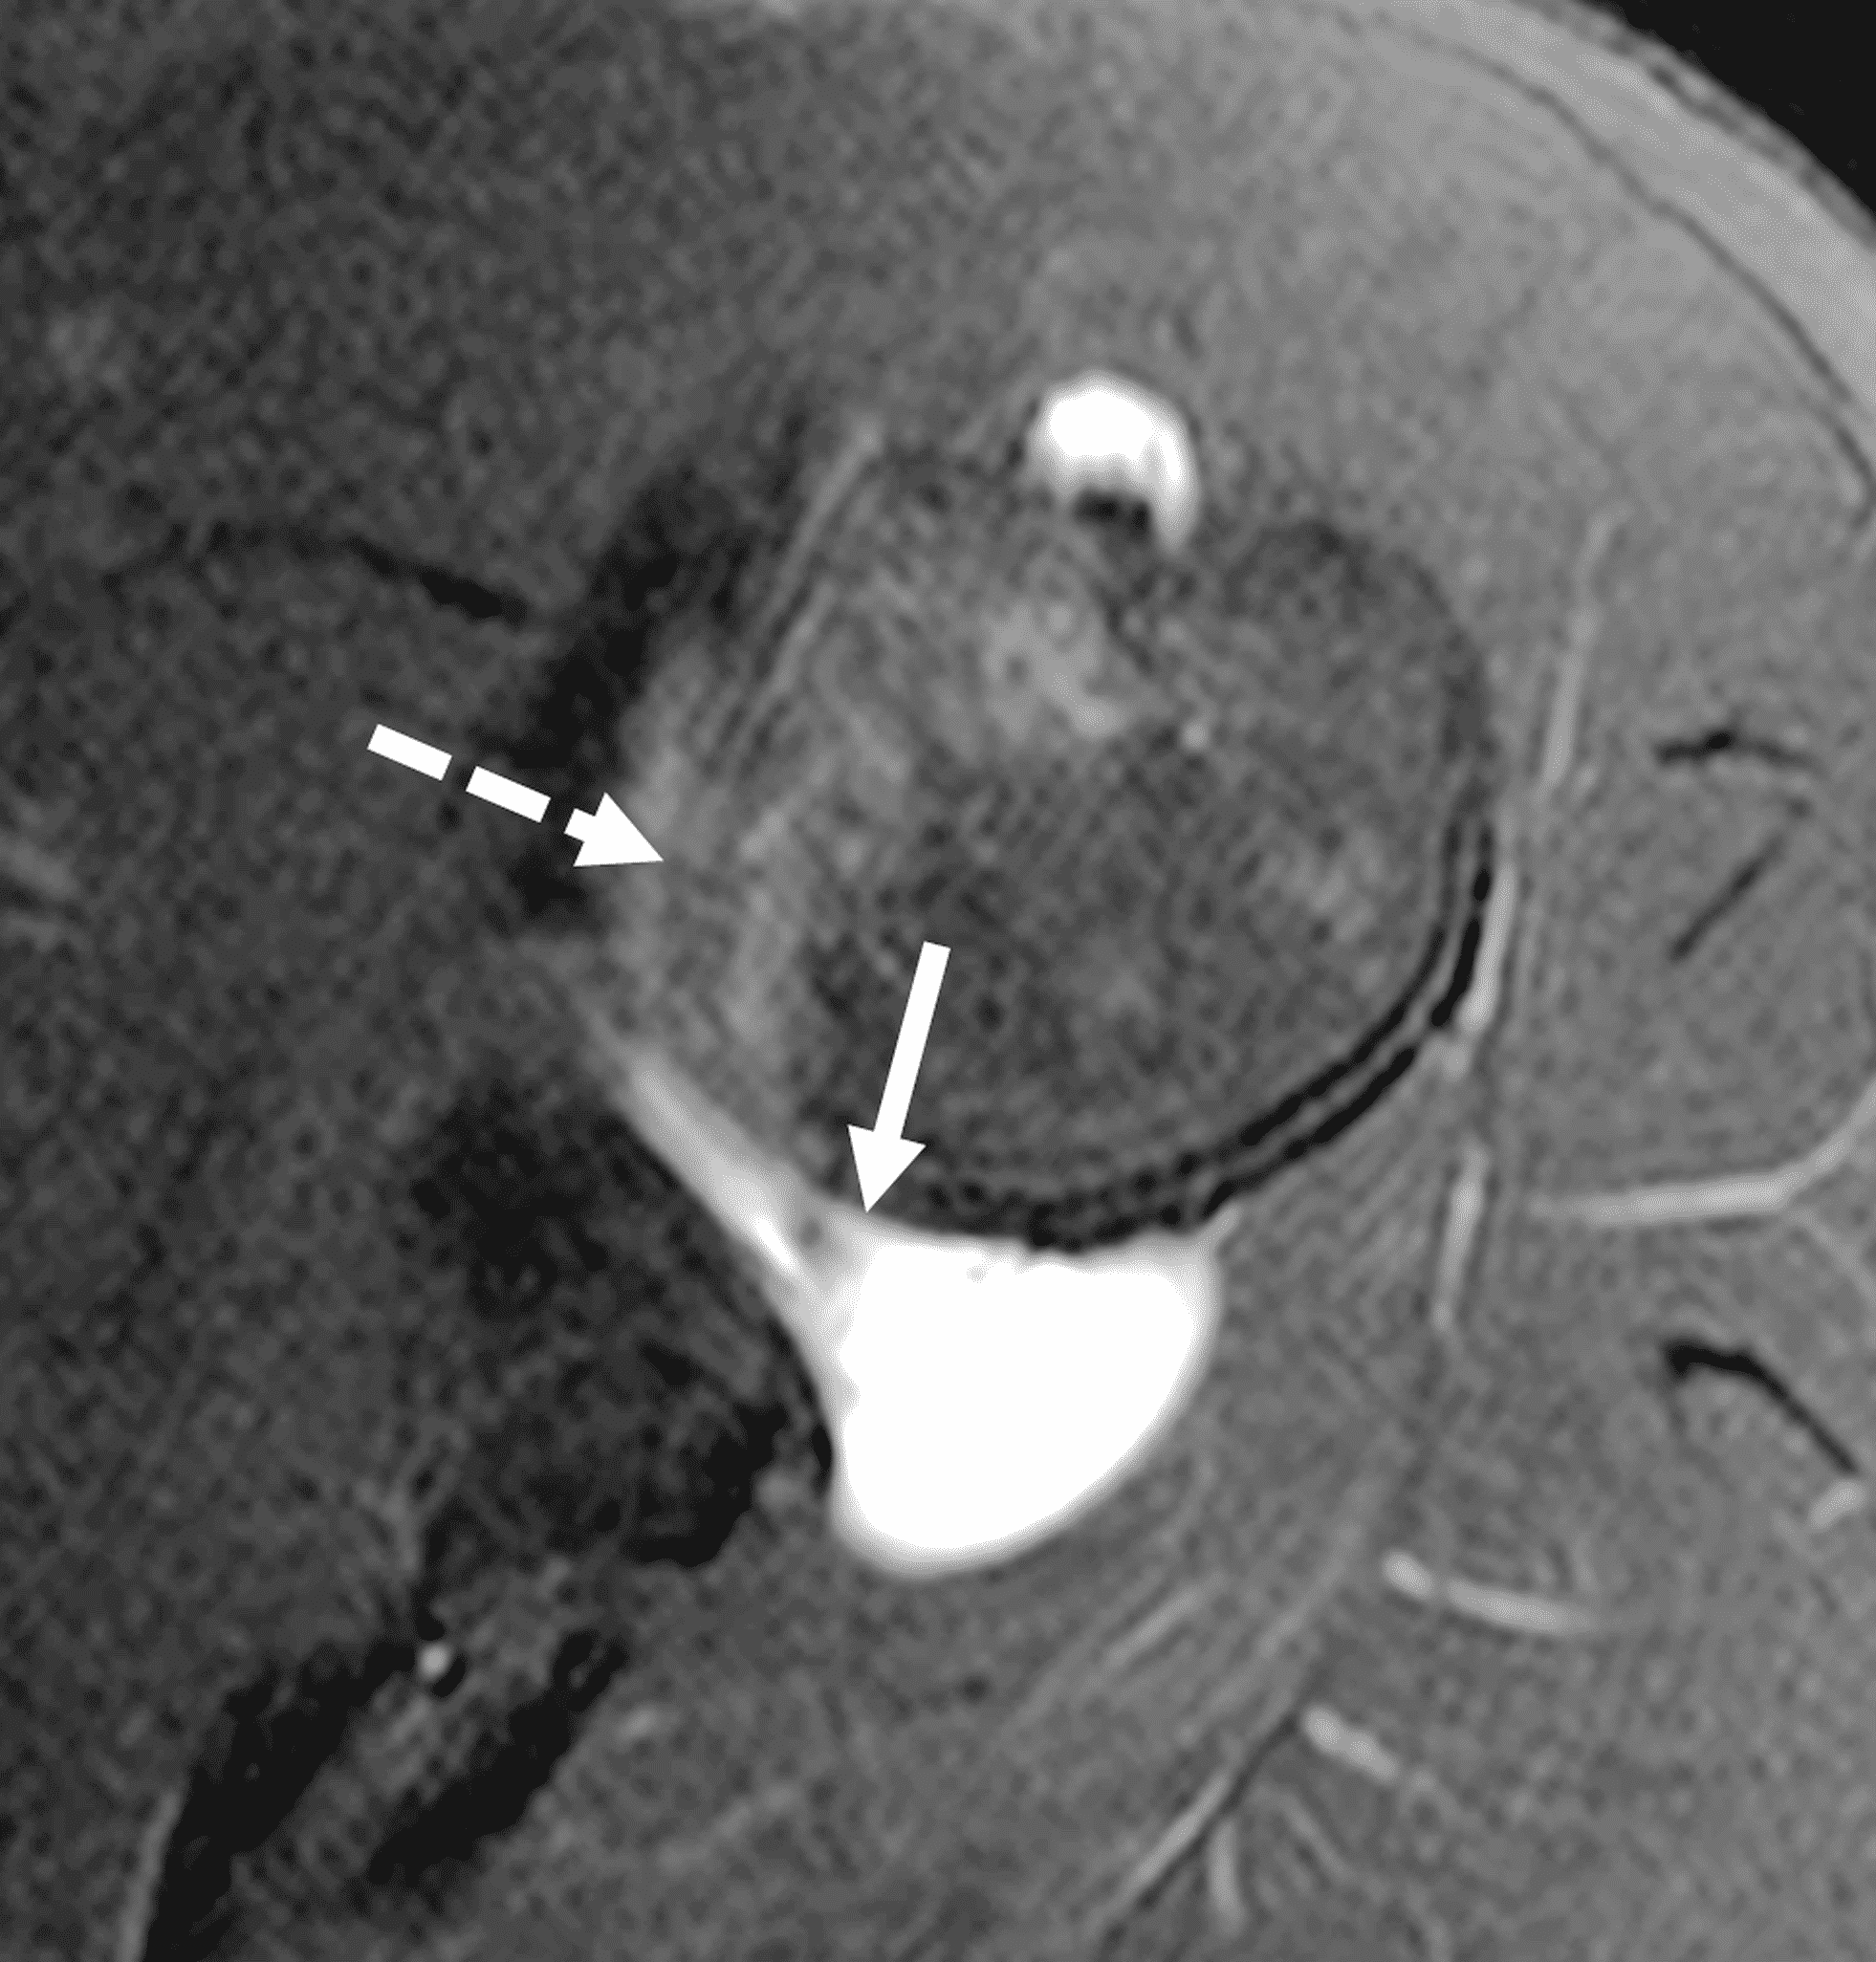

Figure 3: 18 year-old-female college softball player with acute left shoulder batting injury. (3A and 3B) Axial fat-suppressed proton-density-weighted images show a nondisplaced intrasubstance posteroinferior labral tear (solid arrows) and anteromedial humeral head impaction fracture with mild underlying marrow edema (dashed arrows).